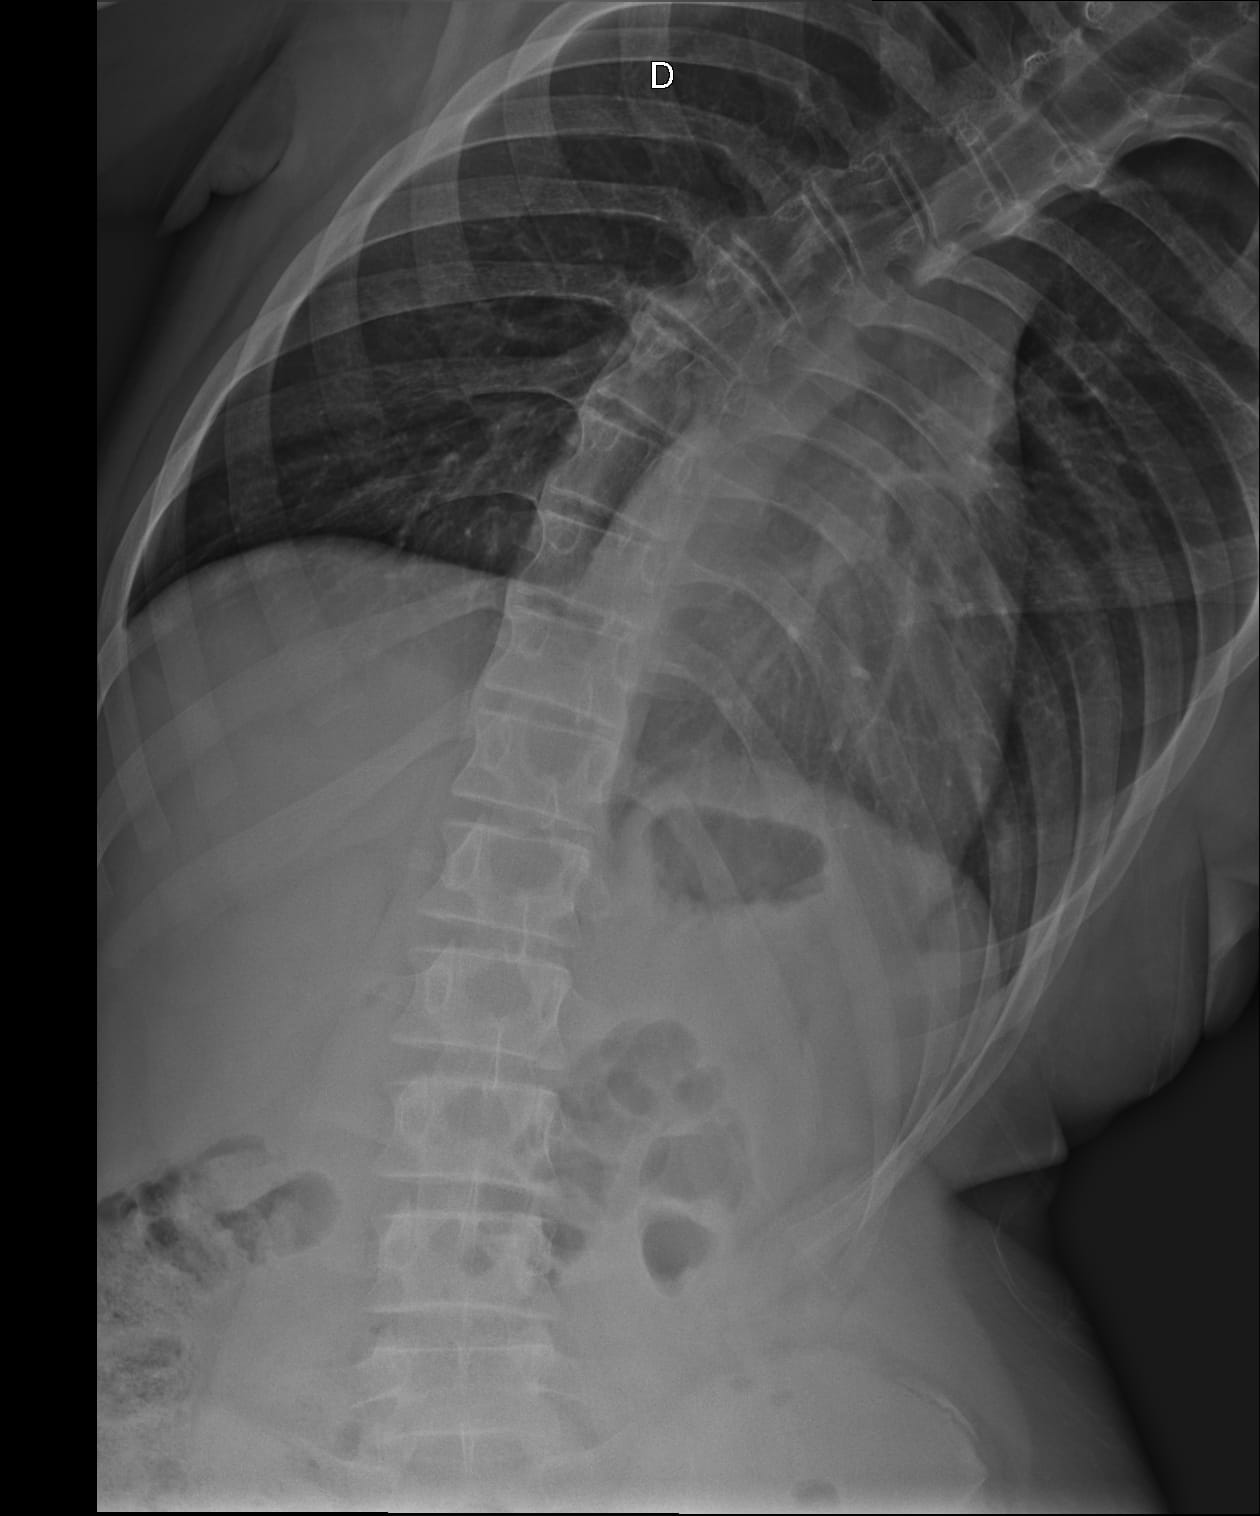

Matheus tem escoliose em grau avançado (curvatura em S de 42 graus), o que tem afetado profundamente sua qualidade de vida. Estamos em uma verdadeira batalha por exames e atendimentos médicos, muitos deles em outras cidades, o que gera gastos com transporte e alimentação que hoje não consigo cobrir.

Além da escoliose, Matheus também precisa de acompanhamento com neuropsicólogo e sofre de asma respiratória, o que exige cuidados constantes. No momento, estamos aguardando uma tomografia da coluna, exame essencial para avaliar a necessidade de cirurgia, conforme já indicado pelo médico. Também preciso providenciar óculos novos para ele, mas infelizmente estou sem condições financeiras.